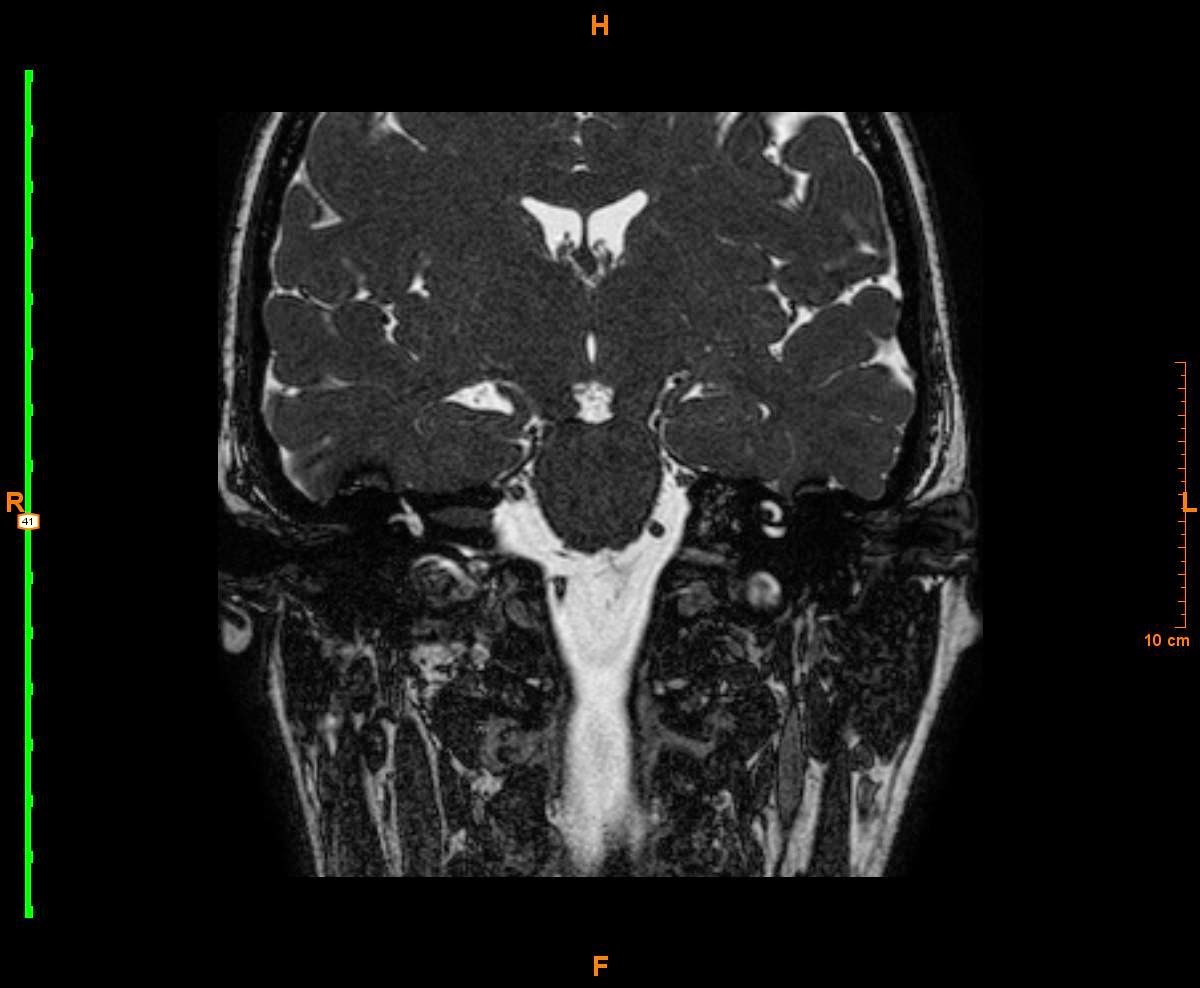

Así es como llega a nuestra cita de RM donde se le realiza un estudio específico para valoración del ángulo pontocerebeloso que incluye las secuencias referidas en los comentarios (FFE T1 3D sin y con contraste intravenoso, B-FFE T2 coronal y DRIVE T2 axial). En estas secuencias realizadas se identifica una lesión que ocupa el CAI derecho, protuyendo hacia el ángulo pontocerebeloso del mismo lado y que sigue el trayecto del VII y VIII pares craneales. Presentaba unas dimensiones de 5 x 15 mm, mostrando una baja intensidad de señal en T2 y realce homogéneo con el contraste, concluyéndose el informe como altamente sugestivo de neurinoma.

Las secuencias de RM de cráneo presentadas son secuencia axial Balance-FFE y secuencias coronales DRIVE, así como secuencia específica de CAIS. Son secuencias eco de gradiente, potenciadas en T2, con cortes finos, que son especialmente útiles para el estudio de los pares craneales y su patología.

En todas estas secuencias podemos evidenciar una lesión nodular dependiente del VIII pc izquierdo me parece que con componente intra y extra canalicular y extensión a la cisterna del ángulo pontocerebeloso, compatible con neurinoma (creo que estadio II o cisternal).